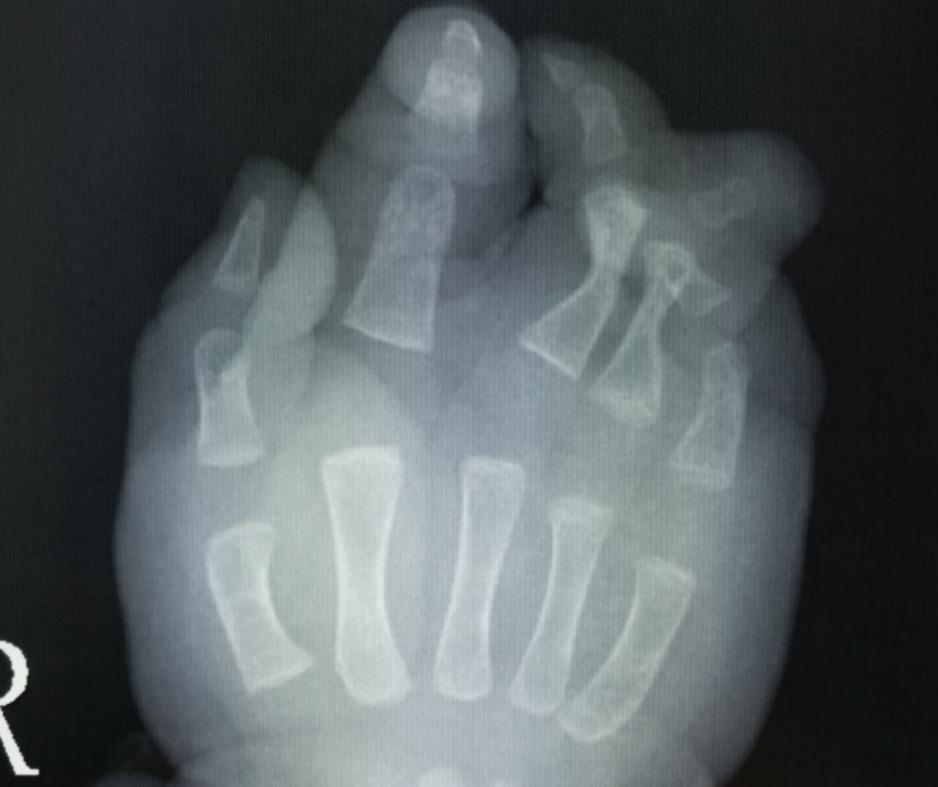

病例7:看到这样的手之后,很多人的第一反应就是怎么只有三根手指,能不能通过手术把三根手指变成五根。其实对于这个孩子的情况,还是要先把并指分开,分开之后可以考虑四根手指,因为通过对比X线片子,我们发现只有三根手指的这个手的第二根手指的指骨和掌骨都比好的那个手指的指骨和掌骨粗,这就意味着这是一个完全的复杂并指。

右手x线

左手x线

如果家长有需求,我们可以给这个孩子进行第二次分指,把三根手指变成四根,分指之后粗细有一定的保障,但是五根手指的可能性不大,哪怕从脚上移植,外观、功能和协调性可能都达不到我们想要的效果,所以四根手指可以探讨,五根意义不大。